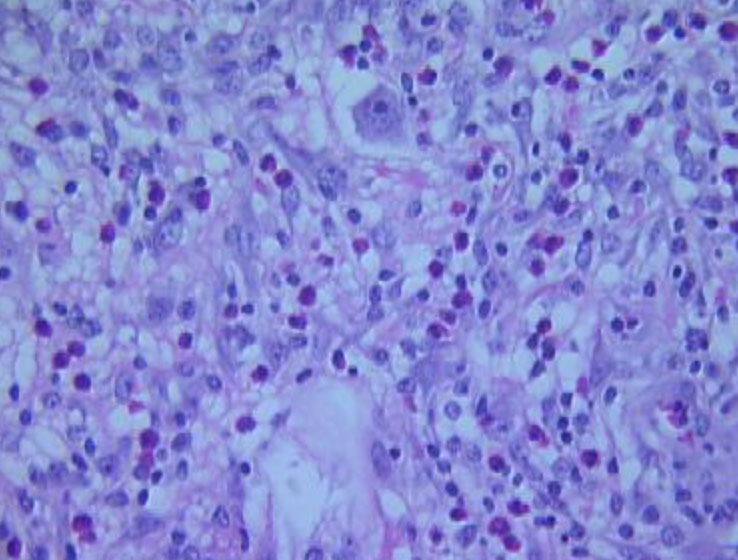

Acute febrile neutrophilic dermatosis (Sweet's syndrome)

Assoc c myeloprolif dz, pts get red hot lesions after a URTI

- clinically presents as painful, dark red crusted plaques / nodules and assoc fevers

Micro: Marked edema of the papillary dermis (like a pink band under the epidermis) and neutrophilic dermal infiltrate

- Focal LCV (similar to below, but not necessarily effecting vessels) c space-dust neutrophils often seen

DDx: infx (should r/o c stains or culture)

Sweet's syndrome